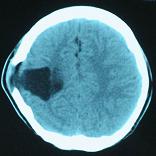

頭顱CT和MRI可見顱骨缺損區(qū)下方軟腦膜囊腫、腦軟化灶或腦室穿通畸形(圖2)。

圖2:①和②CT及骨窗相顯示右頂部顱骨缺損,其下方腦組織呈低密度改變;③-⑥MRI右頂局部顱骨缺如,腦組織輕度向外膨隆,右頂葉側(cè)腦室體部旁局部腦組織缺如,代之以囊性長T1、長T2信號。

結(jié)果及隨訪:術(shù)后一周復(fù)查頭顱CT顯示腦室穿通畸形明顯縮小(圖6)。隨訪3年,未出現(xiàn)癲癇發(fā)作。得到很好的治療,回歸社會,正常生活學(xué)習(xí)工作。

圖6:術(shù)后一周復(fù)查頭顱CT顯示腦室穿通畸形明顯縮小